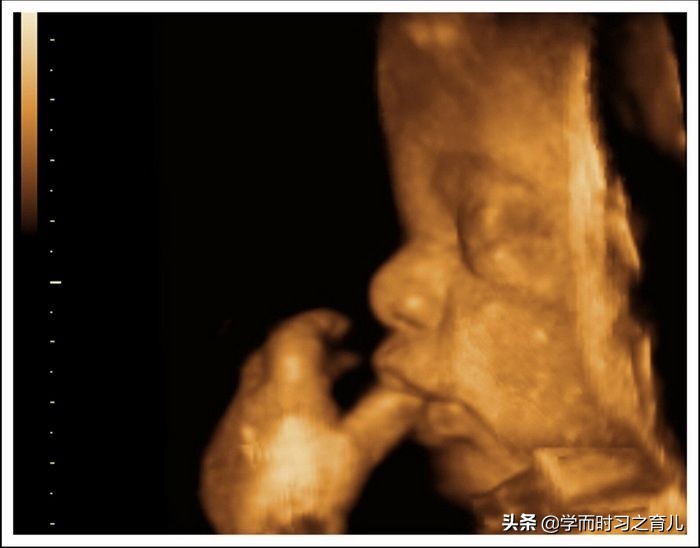

虽然四维彩超已经是目前最先进的技术了,不仅可以检查胎儿的发育情况,还可以实时看到胎宝宝的各种动作,但这还是无法检查出胎儿所有的畸形,存在一定的局限性。

做一次胎儿大排畸,常常会花费很长的时间,这是因为要检查的部位比较多,有时还有可能碰到胎宝宝不配合的情况加长检查时间,当然了,也不是说医生要检查胎宝宝所有的器官,像有些器官并不在超声检查范围之内,比如胎儿的耳朵、腭弓、生殖器等等。